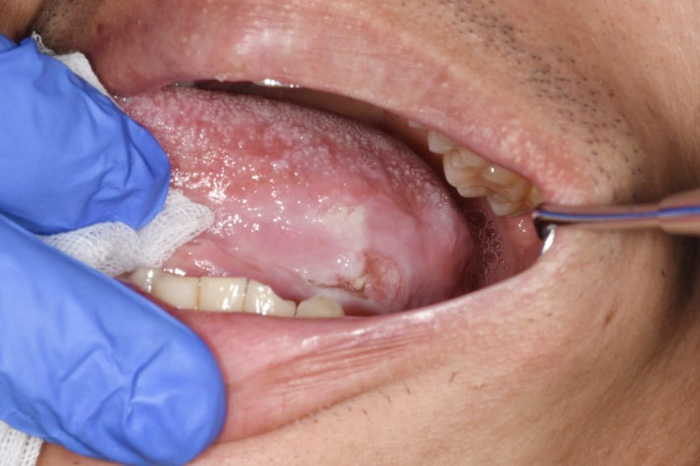

令和4年から口腔腫瘍科を新たに開設させていただきました。口腔腫瘍科で主に扱う疾患は口腔がん(舌がん、歯肉がん、頬粘膜がん、口蓋がん、口底がんなど)です。また、口腔潜在的悪性疾患としての前がん病変(白板症、紅板症など)や、前がん状態(口腔扁平苔癬)なども取り扱います。治療については手術療法、化学療法、放射線療法などを疾患により組み合わせて行います。広範囲にわたる手術などは関係各科と連携・協力し適切に進めていきます。

代表画像(舌がん)

舌がん

治療後(前腕皮弁で再建)